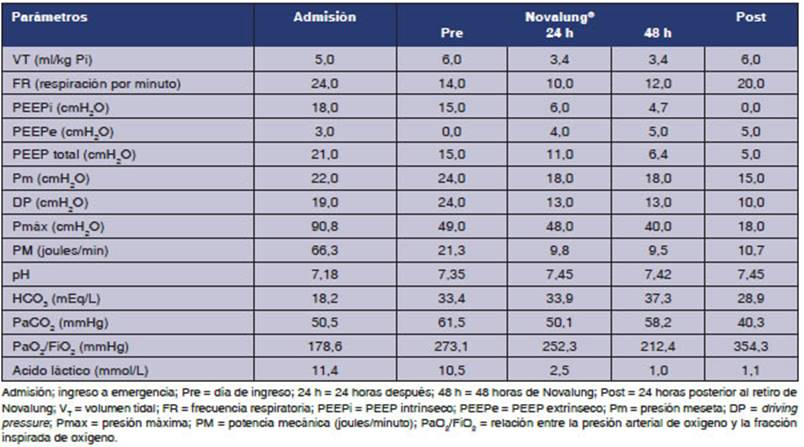

Una

vez en Novalung®️, se aplicó el modo conÂtrol

por volumen con VT 300

ml y FR 10 rpm. El flujo sanguíneo del Novalung® se mantuvo

entre 1,2 L/min y 1,6 L/min y el flujo de barrido se ajustó entre 6

L/min y 7 L/min. El día de la conexión, la relación PaO2/FiO2, la PaCO2 y el pH se

muestran en la Tabla 1. Veinticuatro horas después de la conexión

a Novalung®️,

la presión máxima (Pmáx) de las

vías respiratorias se redujo y la oxigenación permaneció

sin cambios. Las modificaciones más importantes fueron la caída

de la PEEPi y de la Pmáx

(Figura 1).

El

paciente permaneció 10 d en Novalung®️ y mostró

buena evolución. A las 72 h de la retirada del Novalung®, se extubó. Sus parámetros ventiÂlatorios previos

a la extubación fueron: Pmeseta

= 15 cmH2O;

DP = 10 cmH2O;

Pmáx = 18 cmH2O y PM de 10 J/min, sin PEEPi. Los parámetros gasométricos fueron pH

= 7,44, PaCO2 = 39,6 mmHg, PaO2 = 71,9 mmHg. Dada su estabilidad, el paciente fue dado de alta de

la UCI a las 120 h de la extubación,

habiéndose revertido el broncoÂespasmo.

El

principal hallazgo fue identificar la potencia mecánica resistiva como

el principal responsable del brotrauma en un paciente

con EA. Se observó una notable correlación entre el PEEPi y la Pmáx de la

vía aérea, las que disminuyeron drásticamenÂte cuando

logramos bajar la FR, reducir el VT

y prolongar el tiempo espiratorio (relación I:E = 1:7) después de instalar el Novalung®.

Luego de introducir este dispositivo se pudo reducir la FR de 24

rpm a 10 rpm, con lo cual la PEEPi se redujo de 15

cmH2O a 6 cmH2O.

Este cambio atenuó la hiperinsuflación

pulmonar y probablemente redujo la presión intratorácica,

lo que mejoró el retorno venoso y el gasto cardíaco; esto se vio

reflejado en la mejoría de la perfusión clínica, la

diuresis y la corrección del ácido láctico. El control de

la acidosis debería reducir la VPH y la poscarga

del ventrículo derecho8 (Tabla 1).

Estos pacientes, a menudo, tienen un trabajo respiratorio

aumentado, están deshidratados y desarrollan acidosis láctica, lo

que agrava la aciÂdosis respiratoria. Todos estos elementos estaban presentes

en nuestro paciente al ingreso, por lo que recibió cristaloides,

norepinefrina y niveles bajos de PEEP (Tabla 1).